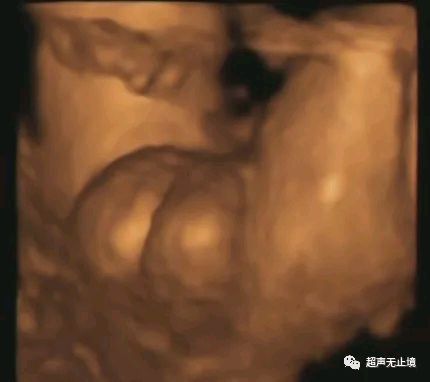

“郁金香征”为胎儿严重尿道下裂表现,代表短小弯曲的阴茎位于分裂的阴囊之间